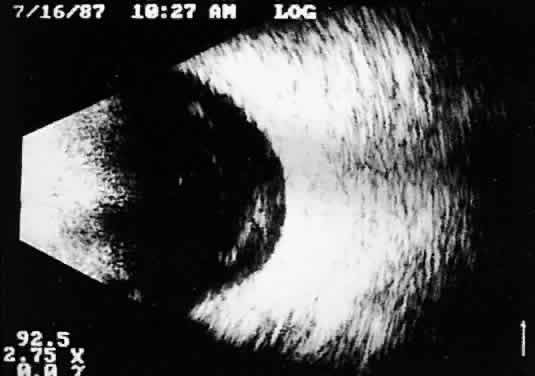

Calcification in any type of tumor tissue creates a strong acoustic interface, resulting in high-amplitude A-scan patterns as well as white echoes in B-scan imaging. Behind the area of calcification, there is usually partial or complete shadowing of the sclera and orbital fat. Bony tumors of the choroid, some retinoblastomas, and drusen of the optic nerve head are typical examples where calcification may be found (Fig. 13).

Fig. 13. Contact B-scans. A. Choroidal osteoma, demonstrating orbital tissue shadowing. B. Dislocated lens. Note shadowing of orbital tissues directly behind the highly reflective lens.